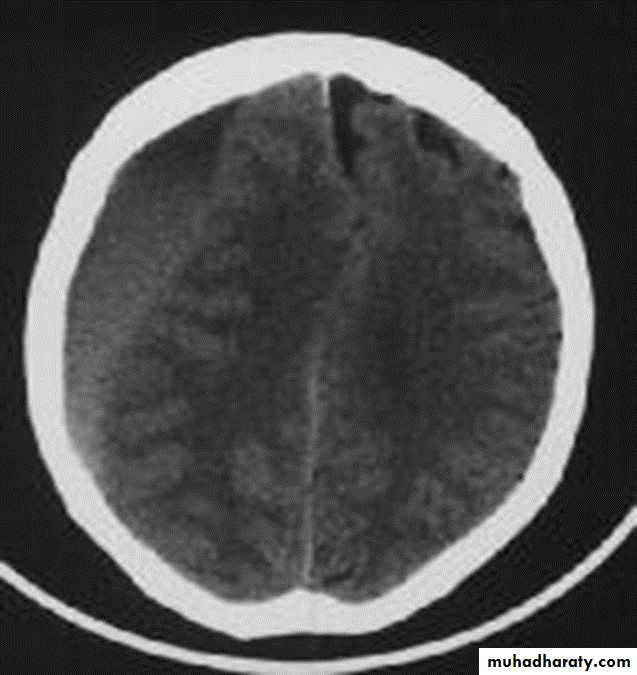

2.cerebral swelling

3.evidence of cerebral anoxia , loss of gray –white interface

Diffused post traumatic bleeding in the subarachnoid space resulting from acceleration decceleration global forces ,the patient presents with agitation and LOC. Treatment is conservative plus measures to decrease intracranial pressurePenetrating head injuries